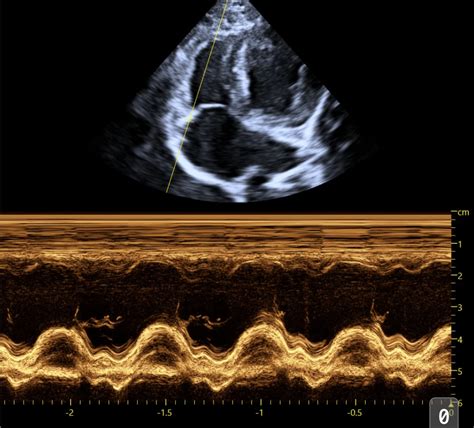

1. The Parasternal Long-Axis View (PLAX)

Alright, let’s start with the parasternal long-axis view , often called the PLAX. This is probably the most fundamental view you’ll learn. We get this by placing the ultrasound probe on the chest wall, typically to the left of the sternum, between the ribs. The name itself gives us clues: ‘parasternal’ means next to the sternum (breastbone), ‘long-axis’ means we’re looking at the heart lengthwise, from the base (where the great vessels exit) towards the apex (the pointy tip). In this view, you guys will see the left ventricle (LV) , the left atrium (LA) , the aortic outflow tract , and the mitral valve . We can assess the size of the LV, its wall thickness, and how it’s contracting. We can also get a good look at the mitral valve’s function and the aortic valve. This view is absolutely critical for assessing systolic function (how well the heart pumps blood out) and diastolic function (how well it relaxes and fills). We often use it to measure things like ejection fraction and fractional shortening, which are key indicators of the heart’s pumping efficiency. It’s like getting a side-profile picture of the heart’s main pumping chamber and its exit route. You can also visualize the interventricular septum and the posterior wall of the left ventricle, comparing their thickness and motion. It’s a fantastic starting point for identifying chamber enlargement, hypertrophy (thickening of the heart muscle), or dilation (enlargement). Don’t underestimate the power of this single view; it provides a wealth of information for initial cardiac assessments. We often begin our systematic scan with the PLAX, orienting ourselves before moving on to more specialized views. It sets the stage for understanding the overall cardiac architecture and function.